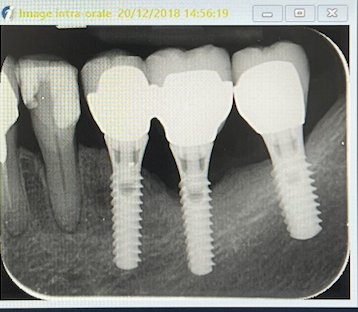

radio le 2O/12/2018

CONCLUSIONS: le protocole DSR associé à une décontamination par l'action conjuguée de H2O2 , Laser semi- pénètrant, 1340 nm et la biostimulation permet d'obtenir une cicatrisation gingivale et osseuse. Ce laser étant peu utilisé maintenant , les protocoles actuels associent laser pénètrant , 980 nm et Erbium 2940 nm